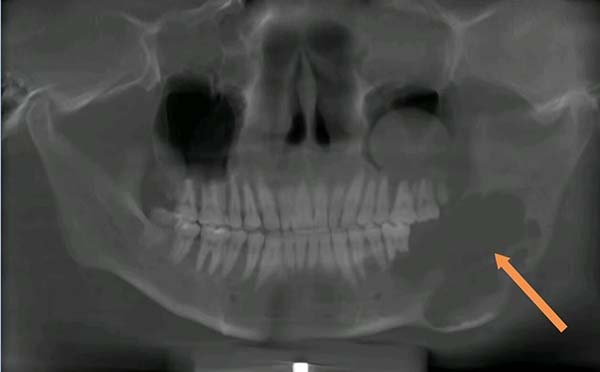

成釉细胞瘤是颌骨常见的牙源性肿瘤,虽然不是恶性,但容易复发、可能恶变,被称为“临界瘤”,多发生于青壮年,逐渐发展可使颌骨膨大,造成畸形,侵犯牙槽突可使牙松动脱落,肿瘤破坏骨质较多,可能发生病理性骨折。

“孩子还小,先试试开窗减压术吧,尽量不在脸上动刀。”黄欣主任耐心跟小元的家人解释。开窗减压术是一种相对保守的治疗方式:在囊性病变表面“开个口”,引流出囊内容物,再用塞治器保持开口通畅,让囊腔内外压力平衡,慢慢缩小,最大程度保住颌骨的形状和功能。

2024年复查时,黄欣主任发现,保守治疗终究没能拦住肿瘤的进展,切除病变的部分下颌骨,成了必须的选择。手术安排在大学暑假的一天,从下午4点持续晚上11点,黄欣、苏明两位专家带领团队,整整忙了7个小时。